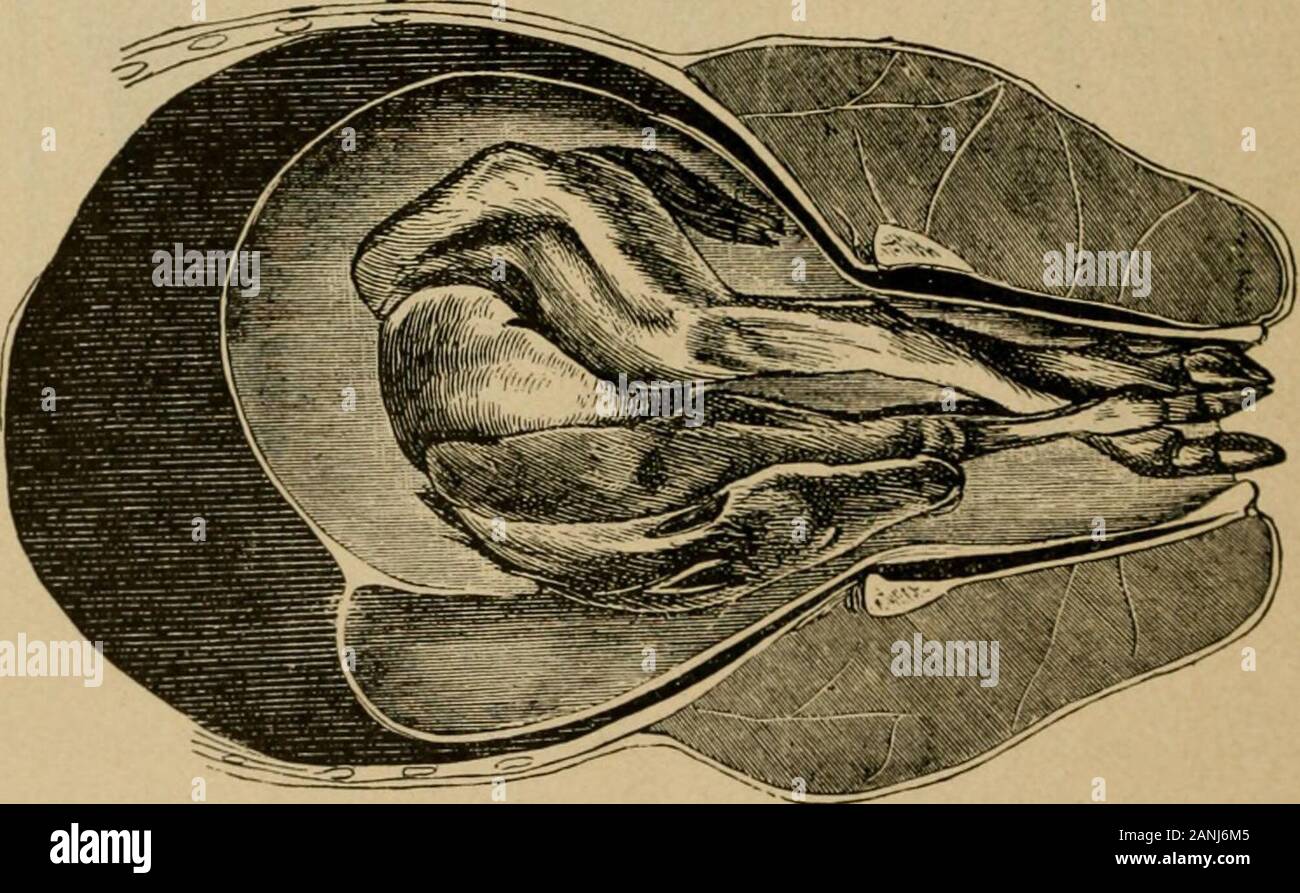

Veterinary obstetrics, including the diseases of breeding animals and of the new-born . Fig. 89. Dorsal Presentation. (Franck).. Fig. 90. Ventral Presentation. (Franck). Positions of the Fetus. Position is the relation existing between an arbitrarily selectedpart of the presenting portion of the fetal body and the circumfer-ence of the pelvic girdle. A fixed point upon the fetal body, thedorsum for the longitudinal presentation, and the head end forthe transverse presentation, is chosen as a basis. The pelvic inlet Positions of the Fetus 533 of the mother is divided into quadrants which repres Stock Photohttps://www.alamy.com/image-license-details/?v=1https://www.alamy.com/veterinary-obstetrics-including-the-diseases-of-breeding-animals-and-of-the-new-born-fig-89-dorsal-presentation-franck-fig-90-ventral-presentation-franck-positions-of-the-fetus-position-is-the-relation-existing-between-an-arbitrarily-selectedpart-of-the-presenting-portion-of-the-fetal-body-and-the-circumfer-ence-of-the-pelvic-girdle-a-fixed-point-upon-the-fetal-body-thedorsum-for-the-longitudinal-presentation-and-the-head-end-forthe-transverse-presentation-is-chosen-as-a-basis-the-pelvic-inlet-positions-of-the-fetus-533-of-the-mother-is-divided-into-quadrants-which-repres-image340305173.html

Veterinary obstetrics, including the diseases of breeding animals and of the new-born . Fig. 89. Dorsal Presentation. (Franck).. Fig. 90. Ventral Presentation. (Franck). Positions of the Fetus. Position is the relation existing between an arbitrarily selectedpart of the presenting portion of the fetal body and the circumfer-ence of the pelvic girdle. A fixed point upon the fetal body, thedorsum for the longitudinal presentation, and the head end forthe transverse presentation, is chosen as a basis. The pelvic inlet Positions of the Fetus 533 of the mother is divided into quadrants which repres Stock Photohttps://www.alamy.com/image-license-details/?v=1https://www.alamy.com/veterinary-obstetrics-including-the-diseases-of-breeding-animals-and-of-the-new-born-fig-89-dorsal-presentation-franck-fig-90-ventral-presentation-franck-positions-of-the-fetus-position-is-the-relation-existing-between-an-arbitrarily-selectedpart-of-the-presenting-portion-of-the-fetal-body-and-the-circumfer-ence-of-the-pelvic-girdle-a-fixed-point-upon-the-fetal-body-thedorsum-for-the-longitudinal-presentation-and-the-head-end-forthe-transverse-presentation-is-chosen-as-a-basis-the-pelvic-inlet-positions-of-the-fetus-533-of-the-mother-is-divided-into-quadrants-which-repres-image340305173.htmlRM2ANJ6M5–Veterinary obstetrics, including the diseases of breeding animals and of the new-born . Fig. 89. Dorsal Presentation. (Franck).. Fig. 90. Ventral Presentation. (Franck). Positions of the Fetus. Position is the relation existing between an arbitrarily selectedpart of the presenting portion of the fetal body and the circumfer-ence of the pelvic girdle. A fixed point upon the fetal body, thedorsum for the longitudinal presentation, and the head end forthe transverse presentation, is chosen as a basis. The pelvic inlet Positions of the Fetus 533 of the mother is divided into quadrants which repres